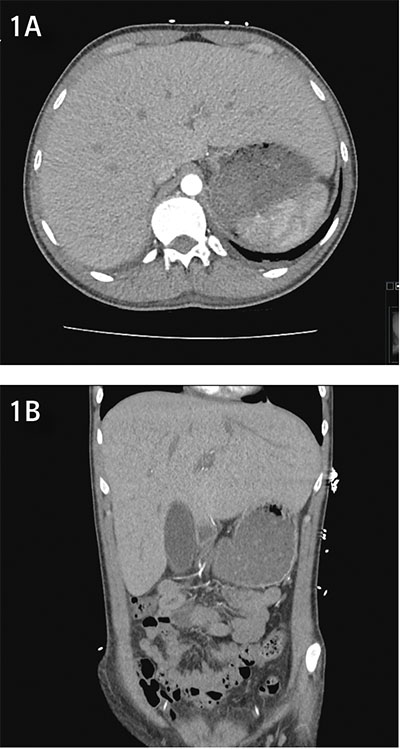

På misstanke om hepatisk glykogenos sekundär till hyperglykemi, och i viss mån på grund av den snabba snabba sänkningen av P-glukos med intravenös insulininfusion i kombination med 10 procent glukos, utfördes leverbiopsi. Denna visade lobulär påverkan med utbredd ballonering av hepatocyter och riklig före­komst av glykogen (Figur 2). Inga belägg för inlagring av fett, järn eller PAS–diastasresistent material noterades. Fynden bedömdes av den erfarne patologen bäst överensstämma med en glykogen hepatopati.

Figur 2. Massiv inlagring av glykogen i levern. A: hematoxylin–eosinfärgning, B: perjodsyra–Schiff (PAS)-färgning för glykogen, C: PAS–diastasfärgning (PAS-D). 20 gångers förstoring i samtliga delfigurer.